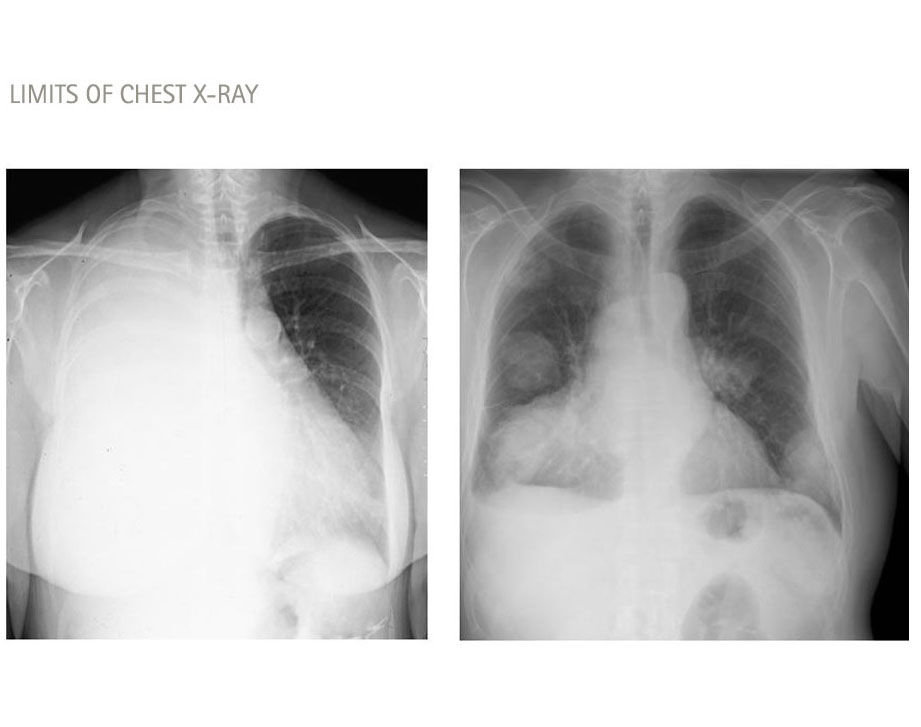

Medica Image to detect misplaced catheter, chest X-ray, alternatively CT or MRI

The main risks of central venous access devices misplacement include infections, bleeding, perforation of the vessel or organ, and difficulty in removing the device. Misplacement can also lead to catheter-related bloodstream infections and thrombosis, which can result in serious complications such as sepsis and pulmonary embolism. Prompt recognition and correction of misplacement are crucial to reduce these risks and improve patient outcomes.

Misplacement/Malposition is one of the most common complications related to  CVADs7-10